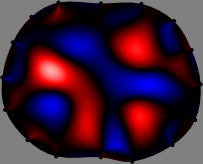

Figs. 3 and 4 compare the performance of the proposed FER method in (20) with the standard regularized least-squares method ((19) when \mathcal{R} is the identity matrix). The regularization parameter of the standard method was heuristically chosen for its best performance, and the parameter of the FER method was set to be one of three different values λ=0.05,0.2,𝜆0.050.2\lambda=0.05,0.2,\infty. The injection current was 1 mARMSRMS{}_{\tiny{\mbox{RMS}}} at 100 kHz, and the frame rate was 9 frames per second. The reference frame at t0subscript𝑡0t_{0} was obtained from the maximum expiration state. The measured data, 𝐕˙(tm)˙𝐕subscript𝑡𝑚\dot{\mathbf{V}}(t_{m}), represent the voltage differences between each time tmsubscript𝑡𝑚t_{m} and t0subscript𝑡0t_{0}. The blue regions, which denote where conductivity decreased by inhaled air, increased during inspiration and decreased during expiration. The FER method with λ=𝜆\lambda=\infty was clearly more robust than the standard method that produced more artifacts originated from the inversion process.

Figure 3: The reconstructed images of the conductivity change of the subject A by the standard regularized least square method and the proposed fidelity-embedded regularization (FER) method for three difference values λ=0.05,0.2,𝜆0.050.2\lambda=0.05,0.2,\infty. Here, the time step is 0.22 seconds (tm+2tm0.22subscript𝑡𝑚2subscript𝑡𝑚0.22t_{m+2}-t_{m}\approx 0.22).